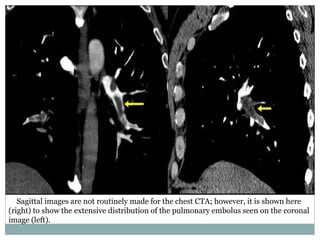

Sagittal images are not routinely made for the chest CTA; however, it is shown here

(right) to show the extensive distribution of the pulmonary embolus seen on the coronal

image (left).

Sagittal images arenot routinely made for the chest CTA; however, it is shown here (right) to show the extensive distribution of the pulmonary embolus seen on the coronal image (left).